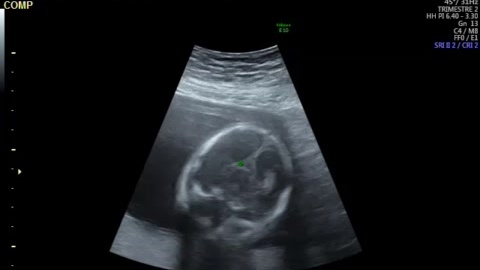

Нам уже 21 неделя (часть 3)